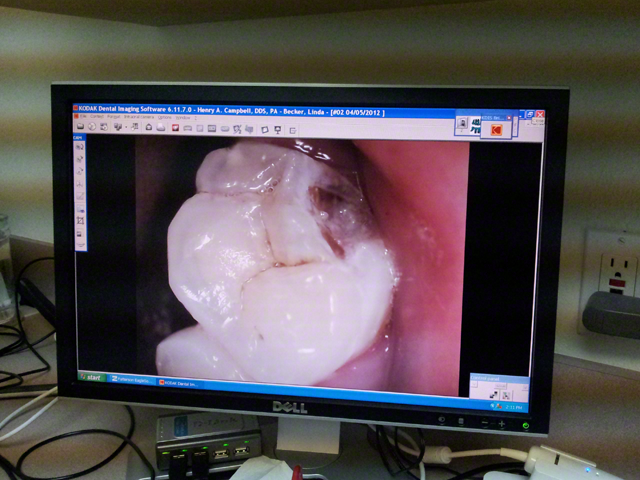

| This was not hurting me. At all. For almost a month. For reals. |

See, I'd chomped part of my tooth off a few weeks before I saw this, but I wasn't sure how bad it was because it didn't hurt, and I could feel my tooth was still there. Granted, it felt a little weird, but I chalked it up to my new nightguard. As in, my THIRD hard acrylic nightguard, because it took me like two years to chew through the first one and four years to chew through the second one, if memory serves me correctly. Yeah, I brux. Horribly. Badly enough to actually break this tooth, apparently.